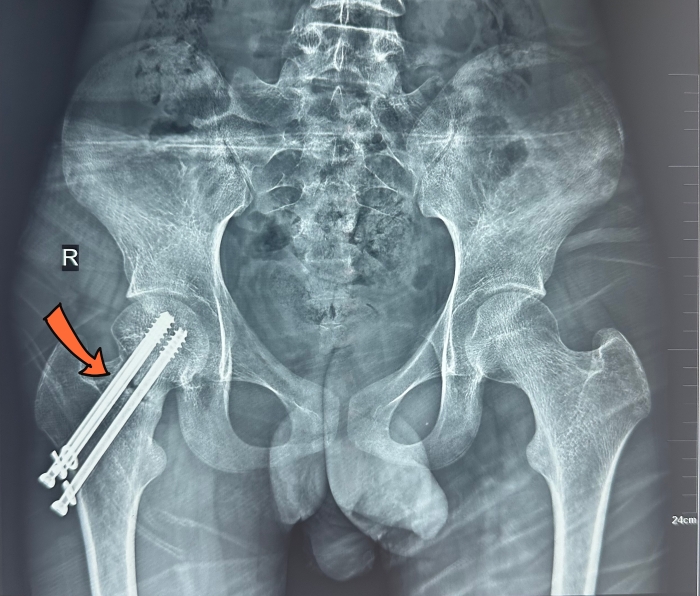

16歲的小吉,8個月前摔傷緻右股骨頸骨折,在當地醫院行股骨頸骨折微創三枚螺絲釘固定術(shù),但(dàn)骨折一直無明顯愈合迹象,且關節出現疼痛,輾轉多家醫院效果不佳。經介紹,他(tā)得(de)知我院骨科(kē)主任姬傳磊經驗豐富,用“帶血管蒂遊離(lí)腓骨移植修複股骨頸骨折”治療效果好,能免除關節置換的痛苦,遂前來(lái)求診。

左/術(shù)前